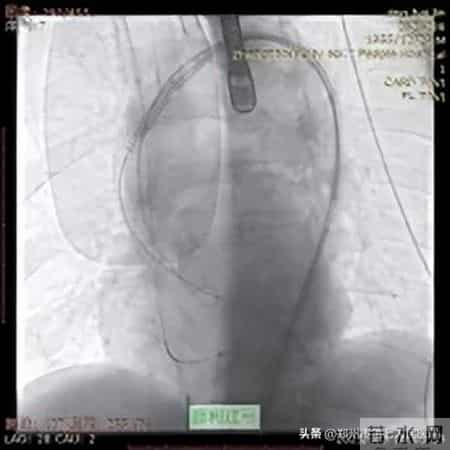

在充分的术前准备之后,手术的大幕正式拉开。在手术过程中,张申伟教授精准操作J-VALVE TF系统,通过股动脉路径微小切口,在“自主导航定位系统”引导下,将人工瓣膜准确输送至病变部位。在释放瓣膜的关键环节,他凭借对系统性能的深刻理解和娴熟的操作手法,精确调整瓣膜位置和角度,确保瓣膜与自体瓣环完美贴合。整个手术过程紧张有序,最终成功完成瓣膜置换。术后,患者心脏功能得到明显改善,第二天即下床活动,最终顺利康复出院。